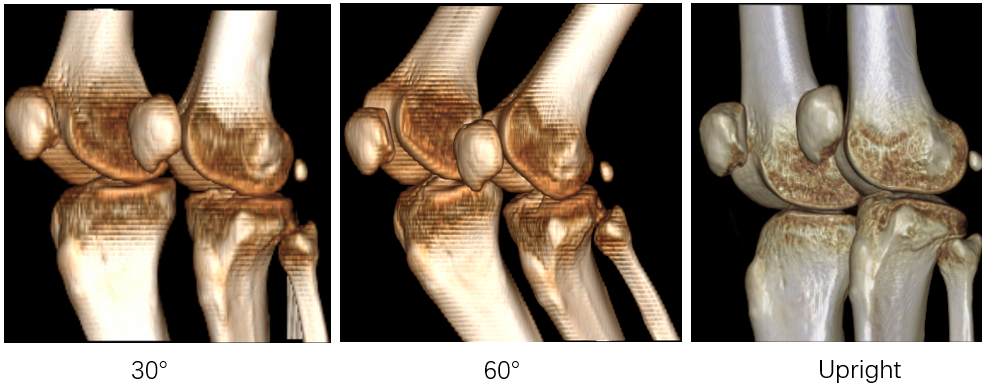

Precise Anchor Location For Cruciate Ligament Surgery

Cruciate ligament connects bone and bone. The role is to strengthen the stability of the joint, so as to avoid injury. When suffering from violence or non-physiological activities, ligaments are stretched beyond their tolerance, resulting in injury.

Cruciate ligament injury is very common in daily life. At present, many ligament reconstruction operations are based on the experience of doctors, and errors are inevitable. Extraction and reconstruction of cruciate ligament insertion is very important, which can help doctors to analyze and predict before surgery, and improve the success rate of surgery.